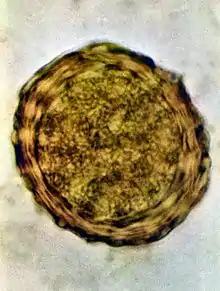

Ascaris lumbricoides is characterized by its great size. Males are 2–4 mm (0.08–0.2 in) in diameter and 15–31 cm (5.9–12 in) long. The male's posterior end is curved ventrally and has a bluntly pointed tail. Females are 3–6 mm (0.1–0.2 in) wide and 20–49 cm (7.9–19 in) long. The vulva is located in the anterior end and accounts for about one-third of its body length. Uteri may contain up to 27 million eggs at a time, with 200,000 being laid per day. Fertilized eggs are oval to round in shape and are 45–75 μm (0.0018–0.0030 in) long and 35–50 μm (0.0014–0.0020 in) wide with a thick outer shell. Unfertilized eggs measure 88–94 μm (0.0035–0.0037 in) long and 44 μm (0.0017 in) wide.[9]